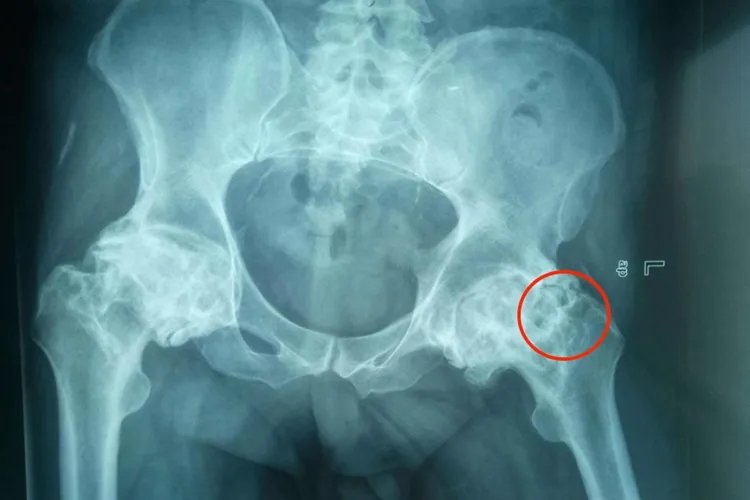

髋关节结核患者存在低热、乏力、倦怠、食欲缺乏等全身症状。起初疼痛不剧烈,休息后好转,小儿表现为夜啼。后期,腹股沟内侧与臀部出现寒性脓肿,破溃后形成慢性窦道。股骨头破坏明显时会形成病理性脱位。股四头肌和臀肌显著萎缩。患者出现屈曲、外展、外旋畸形,随病情发展,髋关节表现为屈曲、内收、内旋畸形,髋关节强直与下肢不等长最为常见。